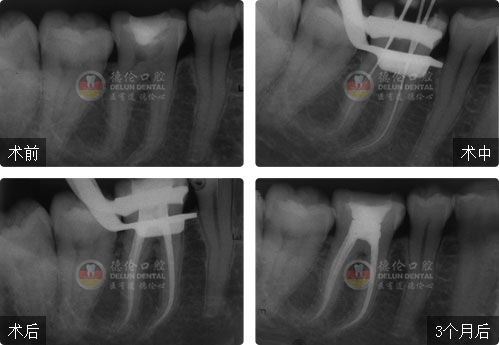

性別:女

年齡:26歲

牙齒癥狀:急性牙髓炎(左下爛牙近一周自發性、陣發性疼痛)

治療方法:顯微根管治療

疑難點評:填充嚴密、各根管均恰填,高質量地完成了彎曲根管和S形根管的治療,體現操作者優秀的臨場操作能力。